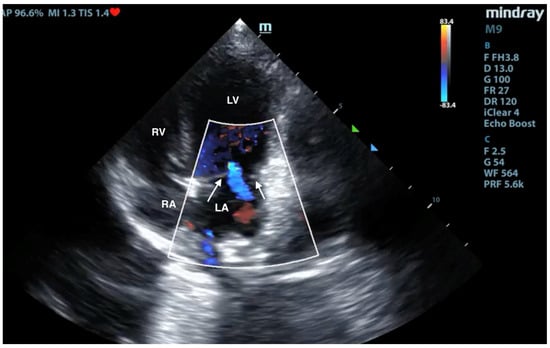

No pathological changes were detected in the lung parenchyma image in the X-ray (Figure 1 and Figure 2). The ultrasound examination revealed in all views a normal, aerated lung pattern. The pleural line was intact, and A-line artifacts were present (Figure 3). The sliding sign was also observed. Echocardiography revealed a mild thickening of the mitral valve leaflets and a slight regurgitation (Figure 4) of this valve. The size of the heart chambers was within the normal range, and myocardial contractility was normal.

Figure 4.

Scan from phased array probe obtained during echocardiography examination performed by a board-certified echocardiography specialist. Mild thickening of the mitral valve and slight regurgitation are visible. The white arrows indicate mitral valve leaflets. LA—left atrium, LV—left ventricle, RA—right atrium, RV—right ventricle.